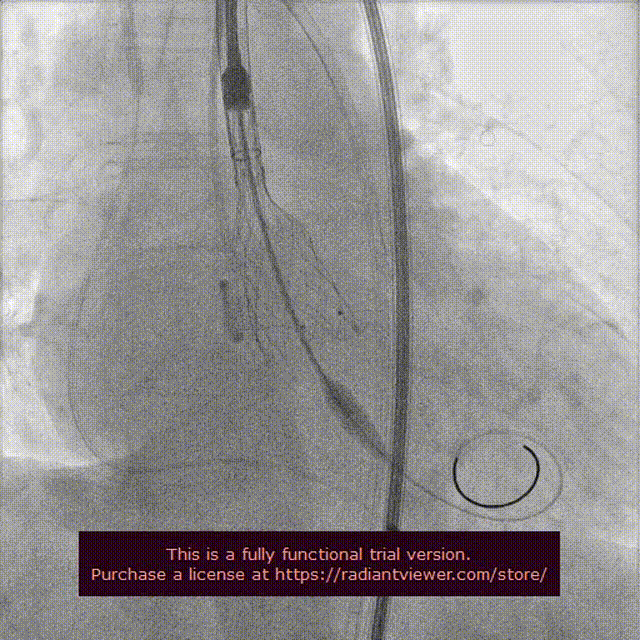

右颈置入保护伞

左颈置入保护伞